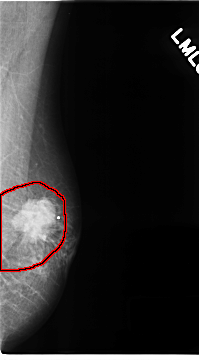

FILE: C_0141_1.LEFT_MLO.OVERLAY

TOTAL_ABNORMALITIES 1

ABNORMALITY 1

LESION_TYPE MASS SHAPE IRREGULAR MARGINS SPICULATED

ASSESSMENT 5

SUBTLETY 5

PATHOLOGY MALIGNANT

TOTAL_OUTLINES 1

BOUNDARY